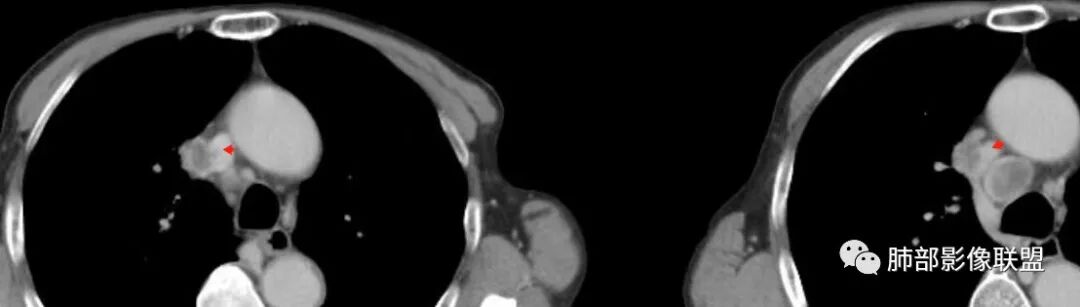

主病灶在右上叶尖段、前段纵隔旁,紧贴胸膜

楔形、边缘膨隆,附近见斑片状、网格状高密度影

支气管近端堵塞,可惜显示的不一定全面

支气管壁还是弥漫增厚

中央坏死明确

如果更薄层一些就好

整体内壁偏清楚,似乎有些地方欠清,不知道是否厚层所致

整体而言:远侧、内侧壁厚

坏死明显,这类膨隆就不支持生长速度不一致所致,而支持坏死朝周围的压力导致边缘的膨隆

这里倒是符合血管的压迫

与胸膜的关系?分界还算清楚

最让人放心不下的是这里

上腔静脉外面按理没有淋巴结啊

其次:团块影的壁:厚薄不均匀

从上面的图看:炎性肯定有

癌?结核?不能排除

这里想看清楚一下